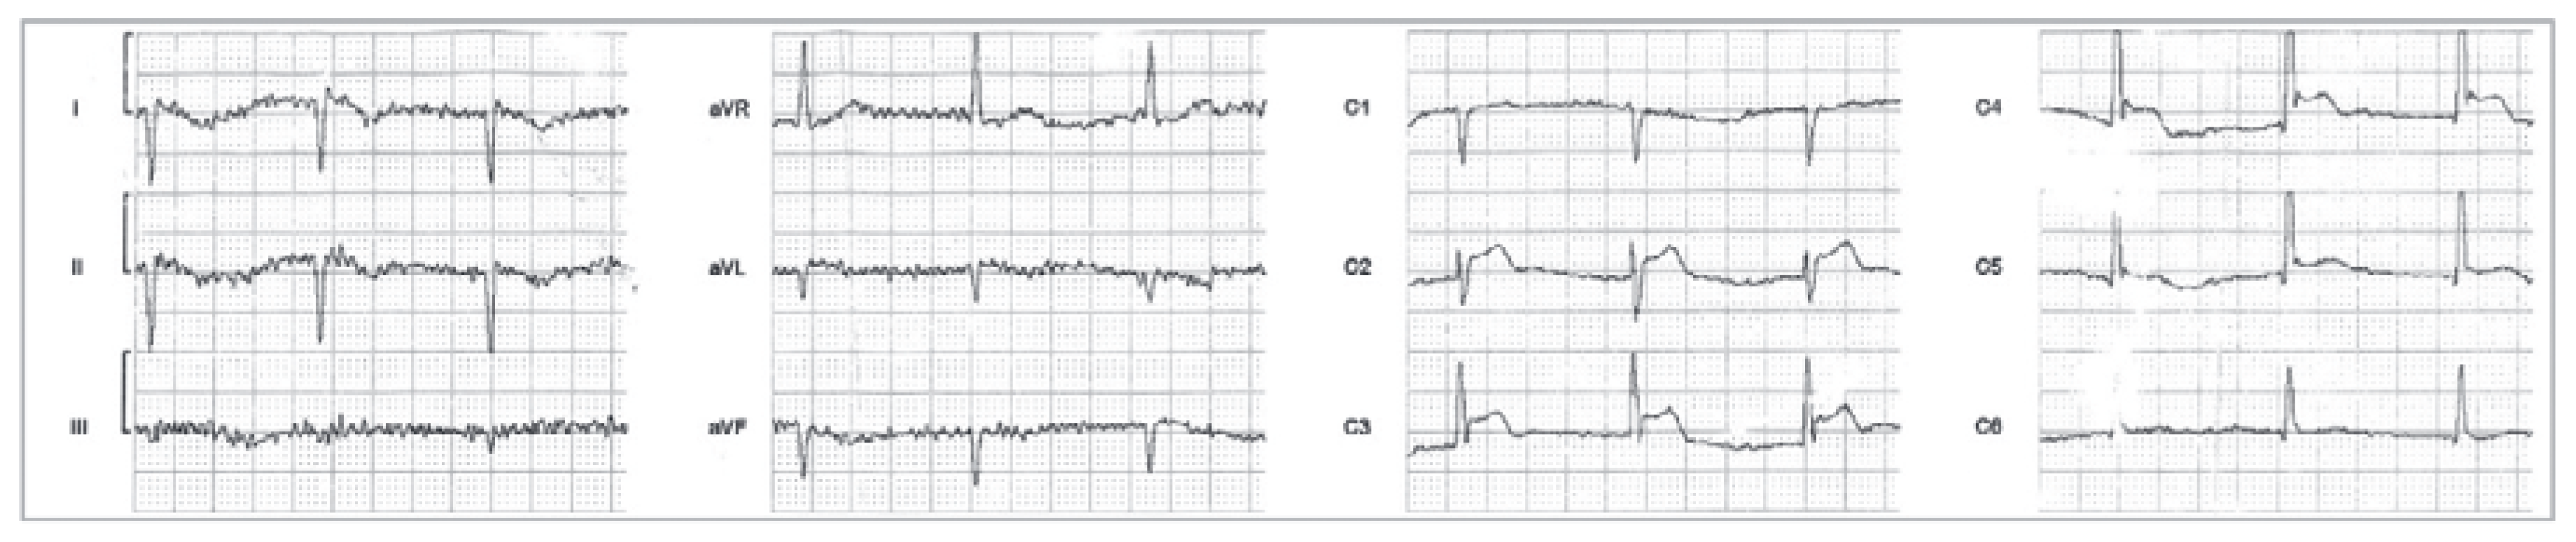

| Transient ischaemic ECG changes during spontaneous episodes, including any of the following in at least two contiguous leads: ST-segment elevation ≥0.1 mV; ST-segment depression ≥0.1 mV; new negative U-waves. |

| Documentation of coronary artery spasm (>90% constriction) during coronary angiography, spontaneously or in response to a provocative stimulus (typically acetylcholine, ergotamine, or hyperventilation); accompanying transient angina and ischaemic ECG changes (as above). |